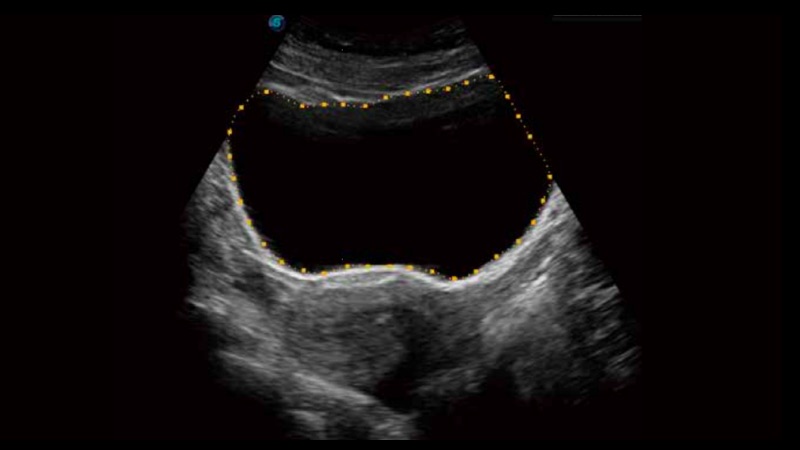

膀胱自動(dòng)測(cè)量,一鍵式膀胱壁追蹤和容量測(cè)量可有效提供更精確的輪廓和結(jié)果,不受膀胱形狀和大小的影響。

自動(dòng)識(shí)別收縮和舒張末期心肌內(nèi)膜,自動(dòng)計(jì)算射血分?jǐn)?shù)EF值。